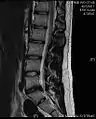

- Magnetic resonance imaging (MRI) without contrast is a diagnostic test that produces three-dimensional images of body structures using powerful magnets and computer technology. It can show the spinal cord, nerve roots, and surrounding areas, as well as enlargement, degeneration, and tumors. It shows soft tissues better than CAT scans. An MRI performed with a high magnetic field strength usually provides the most conclusive evidence for diagnosis of a disc herniation. T2-weighted images allow for clear visualization of protruded disc material in the spinal canal.

MRI scan of cervical disc herniation between C5 and C6 vertebrae.

MRI scan of cervical disc herniation between C6 and C7 vertebrae